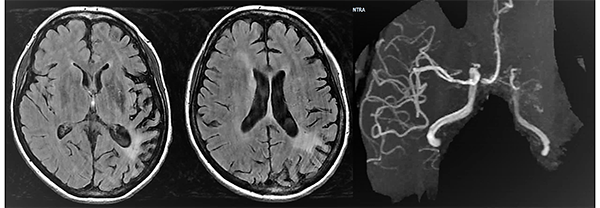

Caso clínico # 2: LD femenino de 51 años con antecedente de tabaquismo e hipertensión arterial, estudiada por deterioro cognitivo de varios meses de evolución. La RMN y ARM evidencia atrofia de hemisferio cerebral izquierdo con hiperintensidad periventricular y disminución franca del calibre de las arterias cerebral anterior y media izquierda con desarrollo de los vasos de MM (Fig. 3). La ADC muestra el stop de la arteria carótida interna izquierda distal y ausencia del origen de las cerebrales anterior y media, buen desarrollo de los vasos de MM y aporte de vasos meníngeos y etmoidales correspondiente a un grado 4 de Suzuki (Fig. 4). Se realizó una revascularización cerebral combinada: un bpTS izquierdo más EDMS y, para aumentar la perfusión en territorio de ambas arterias cerebrales anteriores, un EGPS bifrontal. En la TAC postoperatoria se evidenció un infarto fronto-polar mesial sin repercusión clínica. La ADC postoperatoria diferida evidencia una buena revascularización en los territorios de las arterias cerebral anterior y media a partir del bpTS y la doble sinangiosis (Fig. 5).

Fig. 3 Caso clínico # 2. RMN y ARM preoperatoria, se evidencia atrofia de hemisferio cerebral izquierdo con hiperintensidad periventricular y disminución franca del calibre de las arterias cerebral anterior y media izquierda con desarrollo de los vasos de MM

Fig. 4 Caso clínico # 2. ADC preoperatoria con compromiso bilateral de las arterias carótidas supraclinoidea mayor a izquierda, vasos de MM y presencia de anastomosis leptomeníngeas. Nótese el signo de la botella de champagne en el origen de la arteria carótida interna cervical, presente en los MM avanzados. Corresponde a un grado 4 de Suzuki